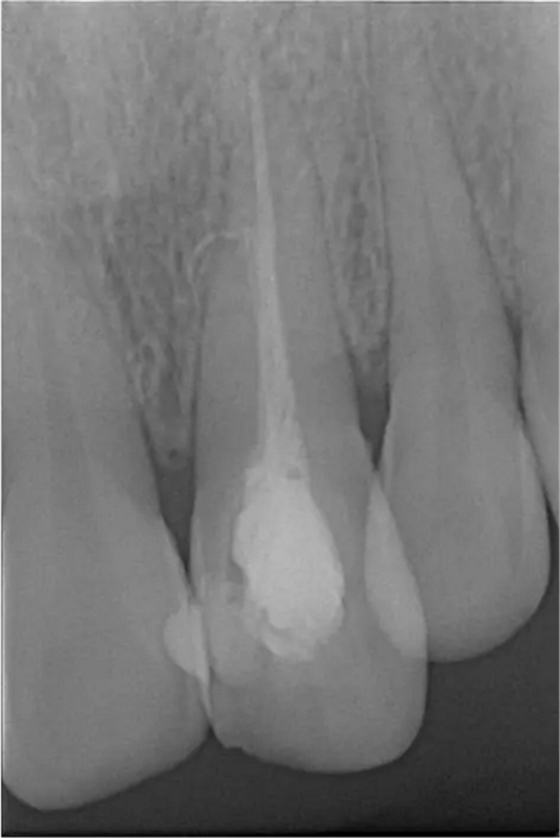

患者女,年齡35左右,牙位21,根管治療曾經(jīng)歷過外院四到五次等不同地方的處理,還是不能咬硬物,會(huì)有酸、軟、痛的情況出現(xiàn),偶有自發(fā)疼痛,2016年9月初,轉(zhuǎn)診至我處治療21。術(shù)前拍片發(fā)現(xiàn)根中部存在側(cè)穿,橡皮障下常規(guī)再治療,隨后減輕了軟和痛的情況。因?yàn)閭?cè)穿,牙周膜受到牙膠尖等異物的持續(xù)刺激,酸軟的情況還是持續(xù)存在,所以決定行根尖外科手術(shù),采用MTA修補(bǔ)穿孔點(diǎn)。術(shù)后觀察半年左右,所有癥狀消除后,隨后熱牙膠充填。

術(shù)前診斷片